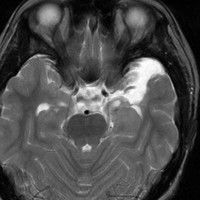

脳幹部から発生した退形成性神経節膠腫 grade 3

軽い右顔面神経麻痺で発症した小児で,右上下肢の軽度の失調症もありました。脳幹部(橋)の右背側から発生した腫瘍で,軽度の閉塞性水頭症を合併しています。左はT2強調画像で,橋の右側ににじむような浸潤像と浮腫があります。腫瘍は小嚢胞を形成してT2強調画像で実質は等信号です。真ん中の画像はCISS画像で橋が腫大しているのがよくわかります。右側はガドリニウム増強像で,全体が増強されてまだらな増強所見となっています。正中後頭下開頭で全摘出 gross total removal して,局所放射線治療とtemozolomide, cisplatine, etoposide, gleevec, hydoreaなどの化学療法を行いましたが,手術後4ヶ月で激しい播種再発を来しました。